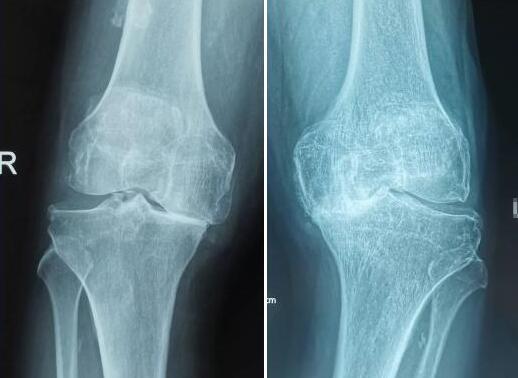

脐带间充质干细胞治疗膝关节软骨磨损效果显著

软骨磨损,是膝关节最常见的慢性进展性关节病。临床表现为膝关节肿胀疼痛,关节持续钝痛,髁软骨损伤患者在跑步、下楼梯时,关节间隙周围均有疼痛,而髌骨软骨损伤患者在上楼梯、半蹲或坐站时,膝关节前方均有疼痛,疼痛程度很重。脐带干细胞用于自身的骨关节治疗,效果显著,大约3个月后,植入的干细胞将逐渐修复受损的膝关节软骨,这项技术的临床治疗过程相当简单,就像打针一样,将干细胞植入膝关节,注射后便可起身行走。